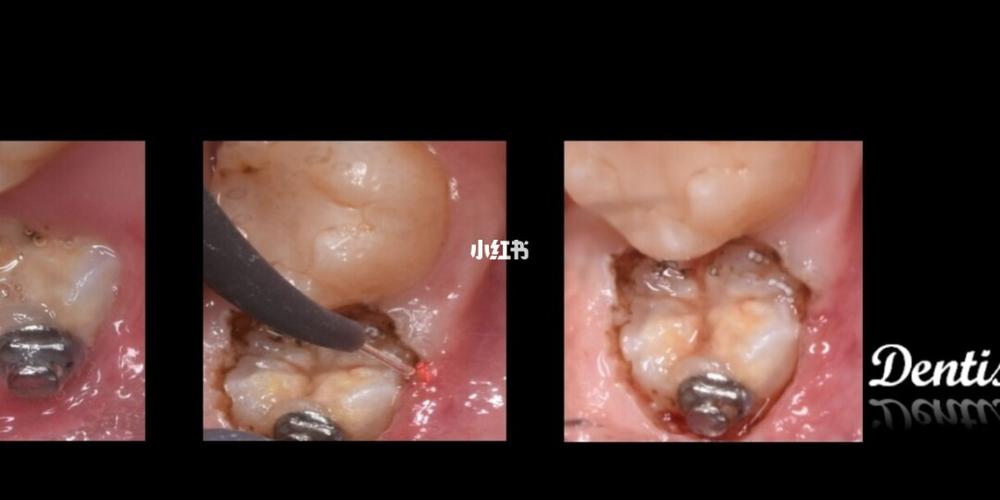

疼痛终结激光神器牙龈切割是一种利用激光技术进行口腔治疗的方法,其最大的特点就是可以无痛进行治疗。这种技术可以快速准确地切除患处组织,创伤小,出血少,恢复期短,同时避免了传统的手术需要使用镊子和刀片的方式进行手术,大大提高了治疗的效率和安全性。

激光技术可以精确地切割组织,并且不会对周围的组织造成损伤,减少了手术后的疼痛和恢复时间,同时也降低了手术的风险。激光技术还可以在手术中实现无血无痛,减少了手术过程中的疼痛和创伤。

与传统的手术方式相比,疼痛终结激光神器牙龈切割的治疗效果更加显著。激光技术可以精确地切除患处组织,避免了手术过程中的误伤和残留,同时也减少了手术后的感染和炎症,大大提高了治疗的成功率。